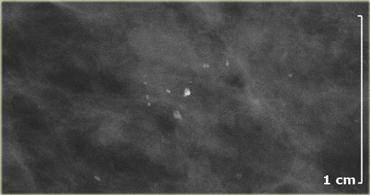

Bên trái là hình ảnh của một bệnh nhân với một vài vôi hóa thô không đồng nhất.

Chúng được phân loại là BIRADS 3 (có khả năng lành tính với xác suất ác tính dưới 3%).

Tại lần theo dõi sáu tháng, số lượng vôi hóa đã tăng lên và kết quả sinh thiết phát hiện DCIS.